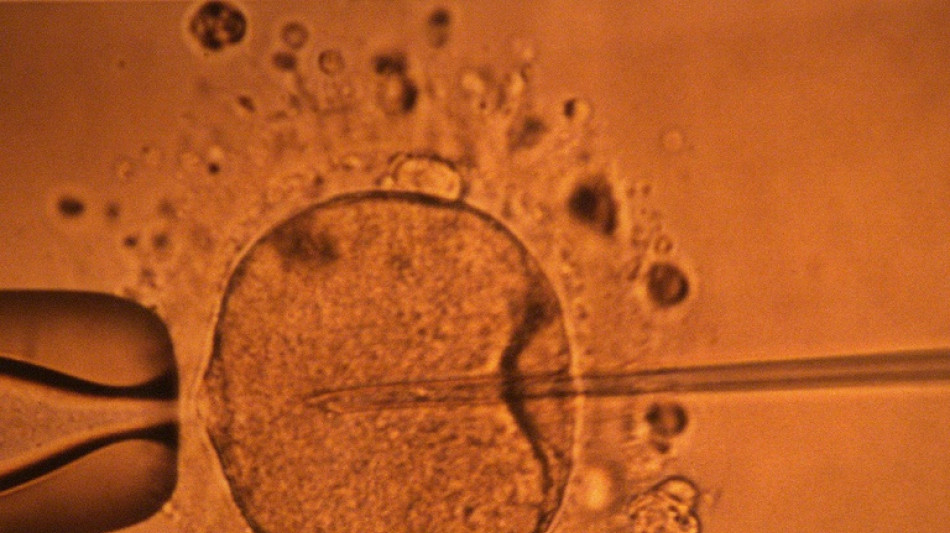

Un estudio apoya hipótesis de disminución mundial de concentración de espermatozoides / Foto: © AFP/Archivos

La concentración de espermatozoides, uno de los factores de la fertilidad masculina, disminuyó significativamente en todo el planeta en las últimas décadas, según un estudio publicado el martes.

"La concentración de espermatozoides disminuyó significativamente entre 1973 y 2018", resumen los autores de este trabajo publicado en la revista Human Reproduction Update y realizado mediante la compilación de unos 40 estudios previos.